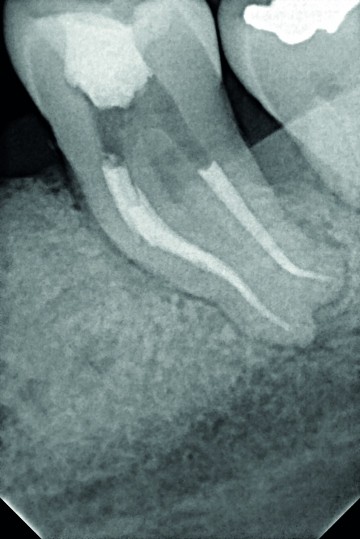

Dr Tara Mc MAHON, Belgium - 1/3 Preoperative x-ray Apical periodontitis, tooth n°37

2/3 Peroperative x-ray Removal of the old restauration and the cavity. Working length (WL) determination.

3/3 Post-operative x-ray Mesial canals: One Curve is used up to the first curvature, rinse. Second wave with One Curve  down to the apex. Distal canal: One Curve direct to the apex, NaOCl 5,25% then EDTA 17%, final rinse with NaOCl before obturation.